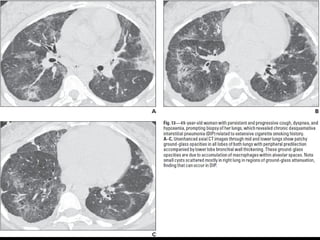

NSIP

• + asociado a otras condiciones esclerodermia,

poliomiositis, dermatomiositis, toxicidad a drogas,

inmunodeficiencia.

• Mejor pronóstico

• 40-50 h=m

NSIP Histología

• Continuo de componente celular a fibrosis

• Plasmocitos y linfocitos

• Engrosamiento intersticial por acumulación de colágeno

• Homogeneidad

• Biopsia es incompatible

con otros patrones

NSIP TC

• Vidrio esmerilado bilat y simétrico, LS

Reticulación fina, BQ por tracción, disminuciónd e volumen pulmonar,

panalización leve

Consolidaciones

Exacerbaciones menos comunes que FPI

• Pronóstico depende del grado de fibrosis

• Celular: 100% sv Fibrótico: 5 años SV